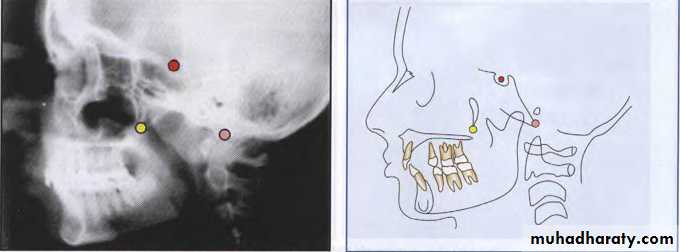

Lateral Cephalometric

• Hard tissue landmarks

Nasion (N)The frontonasal suture at its most superior point on

the curve at the bridge of the nose.

Sella(S)

The center of the hypophyseal fossa (sella turcica). Itis selected by the eye, since that procedure has been

shown to be as reliable as a constructed center.

BILATERAL LANDMARKS

Orbitale (Or)Orbitale has been defined as the lowest point of the

bony orbit. In the PA cephaJogram, each may be

identified but in the lateral cephalograms. the outlines

of the orbital rims overlap. Usually, the lowest point

on the average outline is used to construct the

Frankfort plane.

Gonion (Go)

Gonion is the most posteroinferior point at the angleof the mandible. It may be determined by inspection

or by bisecting the angle formed by the junction of the

ramal and mandibular lines, and extending this

bisector through the mandibular border.

Condylion (Co)

Condylion is the most posterosuperior point on thecondyle of the mandible.

Articulare (Ar)

The intersection of the radiographic shadows:the inferior surface of the cranial base and the posterior

surfaces of the necks of the condyles of the mandible.

Articulare is systematically used for condylion when

the latter is not reliably discernible. Displacement of

the condyle moves the articulare.

Pterygomaxillary Fissure (Ptm)

A bilateral teardrop-shaped area of radiolucency, theanterior shadow of which is the posterior surfaces of

the tuberosities of the maxilla.

Porion (Po)

The "top" of the external auditory meatus. Sometimes,because porion is quite unreliable, the "top" of the shadow of the ear rods is used, which is known as

“machine porion".